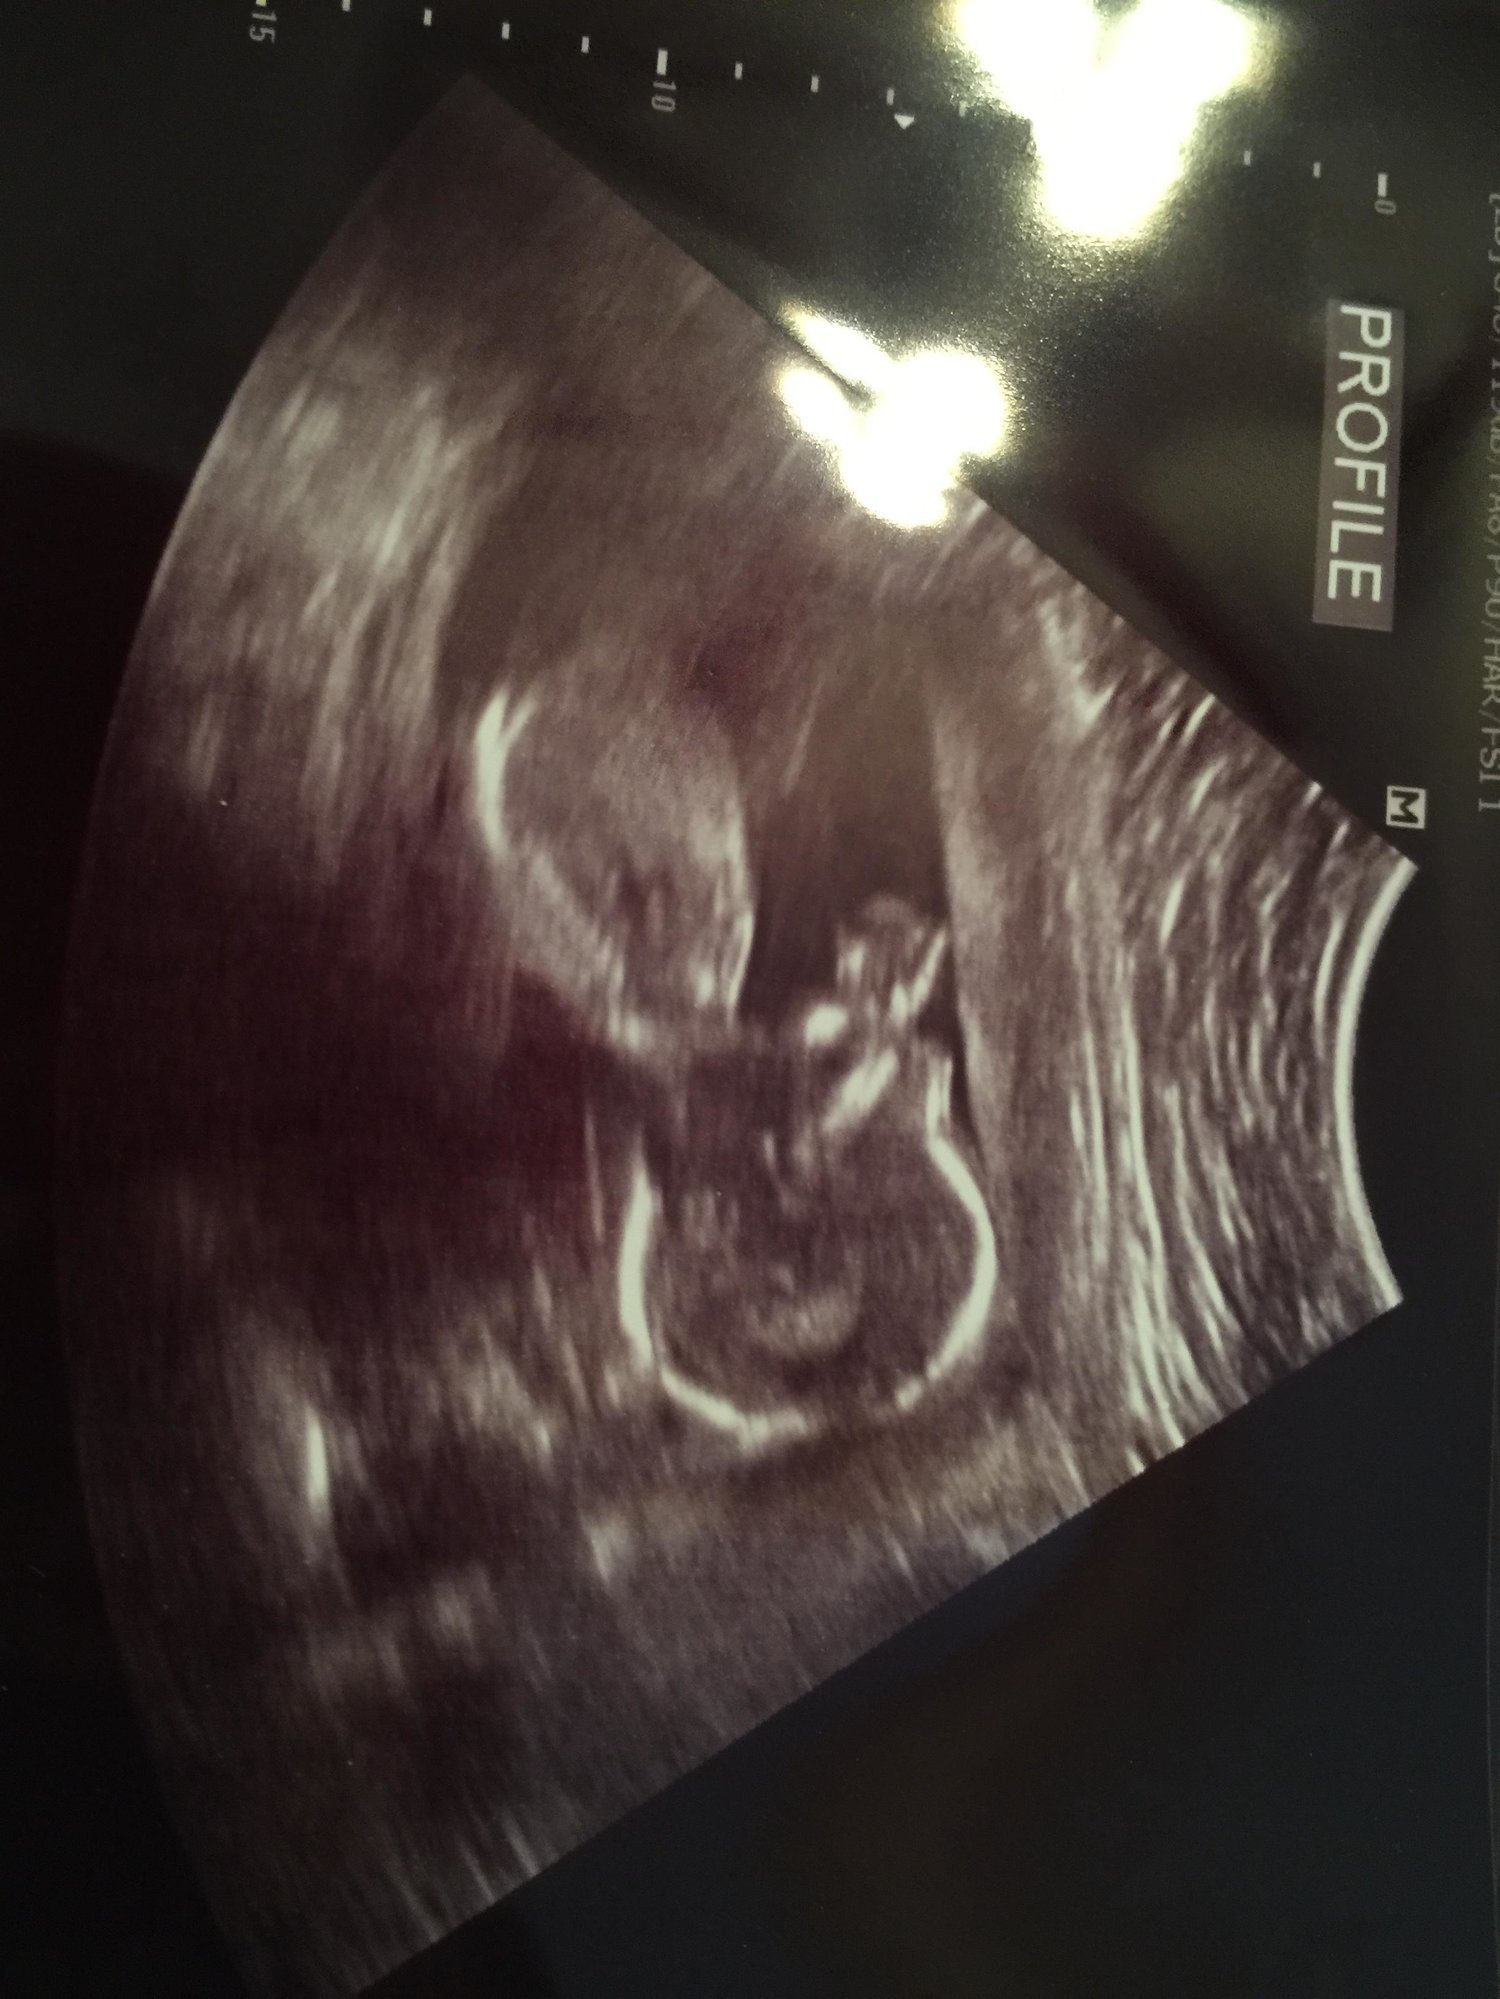

Hoping this works-ive never uploaded on here from a phone. This is sweet baby at 17+5 for our anatomy scan. We aren't finding out sex, so still using interchangeable pronouns and avoiding calling the baby "it". Babies nickname has been Batman since the beginning (cause....why not). Since we didn't get a great face shot to do measurements, I get to go back in 8 weeks for another. Which I am secretly thrilled about. This picture is SUCH a change from babies first photo shoot at 5+6!